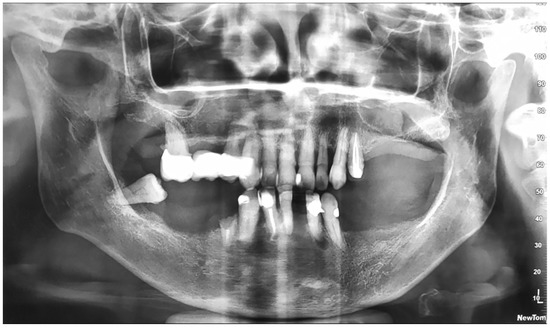

2. Case Report

Surgery Appointment